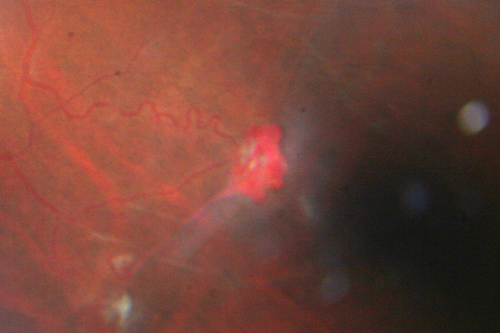

Sickle Retinpoathy SC Disease - Vitreous Hemorrhage Left Eye - 29 Year old

Frond of NV in the periphery